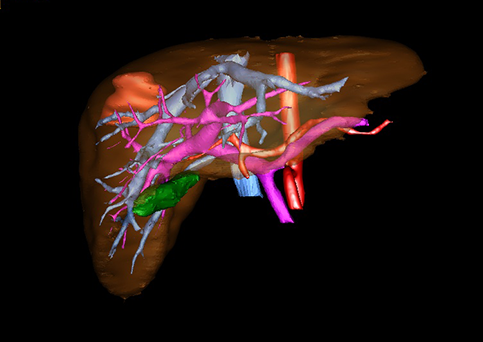

目前常用的检查方法有B超检查、CT、MRI、血管造影等。与其它的腹部肿块的诊断不同,对于小儿肝母细胞瘤血管造影具有重要的意义,可以作为手术前介入治疗的手段,也可为手术提供非常有效的影像学指导,但技术要求高,操作较复杂,且给患儿带来一定的痛苦。近年借助计算机辅助手术系统进行CT原始影像三维重建、手术规划和计算机虚拟手术技术,为精准肝脏手术提供了极为有效的技术支持。

近年来由于数字医学的发展,基于可视化三维重建技术的计算机辅助手术系统极大推进了小儿肝脏肿瘤的精准手术的进步。可以立体透视肝脏解剖、精确掌握肝段的边界、精确测算肝段乃至任意血管所支配的功能体积、准确定位病灶及其与邻近血管的解剖关系,最终对不同手术方案进行比较、筛选和优化。因此,计算机辅助手术规划系统是实现精准肝切除的有力辅助工具,是未来数字外科、精准外科等21世纪外科新理念的重要技术支撑。

计算机辅助手术规划系统具有良好的操作可行性、计算准确性和三维显示效果,可半透明、交互式显示真实的肝内立体解剖关系和空间管道变异,准确计算肝内管道的直径、走行角度,两点间的垂直距离,和任意血管的支配或引流范围等传统二维影像无法获取的信息,有助于实施个体化手术,提高了手术的确定性、预见性和可控性。计算机辅助手术规划系统可直观显示预留肝脏的结构和功能,并可通过虚拟切割功能辅助术者对手术方案进行蹄选和优化,系统评估手术风险和制定对策,改变了部分二维规划的术式和切除范围,使部分二维规划认为不能切除的患者成功手术,提高了手术的根治性、安全性和病变的可切除性,更加符合精准肝脏外科的术前规划要求。详见第11章。

为了更便利地指导床应用,目前国际上肝胆外科的临床医生多采用肝脏Couinaud分类方法。该方法主要以肝门静脉的走行为分类基础,将右前叶分为上下两段,即肝脏分为8段:尾状叶为第Ⅰ段,左外叶分为Ⅱ、Ⅲ段,左内叶为第Ⅳ段,右前叶分为第Ⅴ、Ⅵ段,右后叶分为第Ⅶ、Ⅷ段。了解这些肝脏的分叶和分段法,对于肝脏疾病的定位和手术中血管、胆管系统的正确处理都具有重要的指导意义。见图22。

随着计算机技术及影像检查技术的不断发展,以精确的术前影像学和功能评估、精细的手术操作为核心的精准肝切除技术日益受到重视。基于数字医学的计算机辅助手术技术(computer-assisted surgery,CAS)则是实现肝脏精准手术操作的基础。计算机辅助手术系统(CAS)可将术前二维(two dimensional,2D)的CT/MRI影像数据进行三维(three dimensional,3D)重建,建立个体化的肝脏三维解剖模型,清晰显示肝脏内脉管系统的走行及解剖关系,还原病灶与其周围脉管结构的立体解剖构象,准确地对病变进行定位、定性和评估,制定合理、定量的手术方案,实施个体化的肝脏血管取舍分配方案及实施精准肝脏手术。一般认为CAS包括:创建虚拟的患者的图像;患者图像的分析与深度处理;诊断、手术前规划、手术步骤的模拟;术中实时导航。应用本技术后,由于可以更清晰地看出肿瘤的界限,特别是根据肝血管的显影,判断出肿瘤与门静脉及肝静脉的关系以在手术前较准确地估计出手术成功切除的可行性。以往部分根据普通强化CT判断无法手术的病例而被评估为可以成功切除并手术成功。